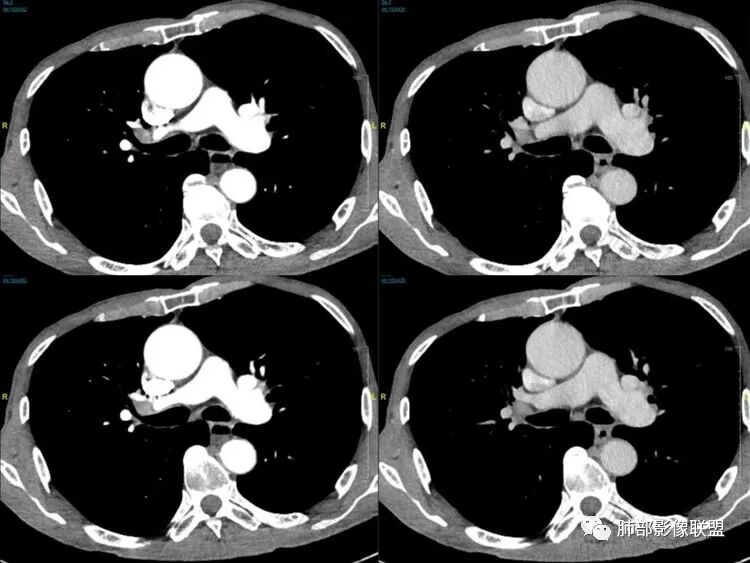

老年男性患者,胸部隐痛1月入院,有长期吸烟史,胸部CT:右肺下叶背段梭型结节灶,边界清晰,无明显分叶、毛刺及周边磨玻璃影,内部密度不均匀,支气管截断,增强扫描不均匀轻度强化,内部似乎见支气管黏液栓,纵隔淋巴结不大,考虑恶性病变:小细胞癌(缺少典型的纵隔肺门淋巴结增大融合),鳞癌(病史复合,但没有阻塞性肺炎,内部没有坏死,),类癌(多见于女性患者,与吸烟关系不大),首先考虑典型类癌,

老年男性,右肺下叶梭形或椭圆形结节,形态较规则,边缘光整,支气管截断,增强不均匀轻度强化,右肺门及纵隔淋巴结增大,考虑恶性病变,鳞癌或小细胞癌,神经内分泌癌(小细胞形)。

老年男性患者,右肺下叶背段梭形结节影,边界比较光整,密度均匀,没有明显的分叶毛刺,没有阻塞性肺炎的表现,这些感觉具备有良性的特点。而近端支气管截断,增强明显的强化,纵隔多发的淋巴结,显得是恶性的特点。总体印象,老年患者+支气管截断征象+明显强化的结节+纵隔多发淋巴结,还是考虑恶性结节,小细胞癌或是鳞癌。

男性,老年人,长期吸烟史,老慢支背景,右下肺背段占位,支气管亚段门口堵,病灶长轴与支气管平行,推测腔内生长可能,病灶内血管穿行,周围干净,轻度强化,右肺门淋巴结肿大,考虑恶性,神经内分泌癌(大小类)>淋巴上皮瘤样癌>腺癌>鳞癌

右肺下叶梭形实性结节,密度均匀,边缘光整,局部膨隆,近端支气管截断,轻度强化,血管走行自然,右肺门及纵隔淋巴结增大,考虑小细胞癌>鳞癌

右肺下叶背段结节,沿着支气管走行呈长椭圆形,边缘圆滑清晰,近端支气管阻塞,远端支气管有沿壁增厚,右肺门淋巴结肿大,中度强化,老年男性,吸烟病史,肺气肿背景,考虑小细胞肺癌,鉴别鳞癌

老年男性,吸烟史,右肺下叶梭形肿块,边缘平直有分叶,支气管近端阻塞,右肺门肿大淋巴结,增强后轻度强化,欠均匀,首先考虑恶性,小细胞肺癌?

老年男性+吸烟+右下肺肿块影+支气管截断+淋巴结肿大,考虑恶性,倾向小

老年男性,吸烟史,右肺下叶背段梭型软组织肿块,边缘膨隆,不均匀强化,近端支气管截断,同侧肺门及纵隔淋巴结肿大,支持恶性,小细胞可能大,鳞癌缺少阻塞性改变

晨读,右下叶梭形占位,边界光滑,支气管截断,可见尾征,不均匀轻度强化,肺门淋巴结肿大,有吸烟史,高龄高危患者,首先考虑恶性,考虑小细胞癌,鉴别一下鳞癌

老年男性,前胸隐痛1月。2年前有白内障手术史。右下肺结节,沿中轴呈梭形,膨隆,边清、无分叶,无毛刺,近端支气管截断完全堵塞,病灶以远未见阻塞性炎症及肺不张。内部密度基本均匀,增强轻微强化,似见局部低密度影。纵隔及右肺门见肿大淋巴结。整体考虑恶性可能性大,小细胞癌?鳞癌?注意鉴别良性结节—错构瘤。

老年男性,长期吸烟史,右肺下叶背段梭形低密度灶,边界清晰,无明显分叶、毛刺,边缘稍彭隆,支气管截断,右肺门淋巴结增大,增强扫描不均匀轻度强化(延迟略明显),首先考虑恶性,小?不典型结核球待排。

右肺下叶背段结节,气管堵塞,密度均匀,边界清晰,无明显分叶、毛刺,边缘膨隆,右肺门淋巴结增大,增强轻度强化,考虑小细胞癌,鉴别鳞癌。

右肺下叶梭形软组织结节,密度均匀,明显尾巴,边缘光整,近端支气管截断,轻度强化,血管走行自然,又腊肠尾巴征象

考虑恶性  小细胞癌?

男,83,前胸部隐痛不适1月。有长年大量吸烟史。胸部CT:肺气肿,右肺下叶纺锤型实性结节灶,边界清晰,支气管截断,内部密度不均匀,增强扫描不均匀强化,右肺门淋巴结大。考虑恶性病变:小?鳞?鉴别炎性肉芽肿、错构瘤等。

晨读:老年男性+吸烟+右肺下叶与气管长轴一致的梭形肿块影+支气管截断,轻度强化,右肺门肿大淋巴结,考虑恶性,小细胞肺癌可能,鉴别鳞癌

呈典型管状改变,近端支气管堵塞、稍扩张,病灶有强化倾向于恶性,没有强化倾向于炎性病变(结核之类);近端呈结节状(鳞癌多一些),这个病例呈管状(小细胞Ca多一些);平扫与强化有差异,有轻度强化,是粘液栓还是血管?

病理结果:小细胞肺癌